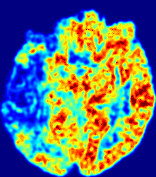

LesionRefer to captionRefer to captionRefer to captionRefer to captionRefer to captionRefer to caption𝐕rgbsubscript𝐕𝑟𝑔𝑏{\bf{V}}_{rgb}Refer to captionRefer to captionRefer to captionRefer to captionRefer to captionRefer to caption𝐕2subscriptnorm𝐕2{\|\bf{V}}\|_{2}Refer to captionRefer to captionRefer to captionRefer to captionRefer to captionRefer to captionRefer to caption3.53.53.52.82.82.82.12.12.11.41.41.40.70.70.70.00.00.0(mm/s)𝑚𝑚𝑠(mm/s)D𝐷DRefer to captionRefer to captionRefer to captionRefer to captionRefer to captionRefer to captionRefer to caption0.0200.0200.0200.0160.0160.0160.0120.0120.0120.0080.0080.0080.0040.0040.0040.0000.0000.000(mm2/s)𝑚superscript𝑚2𝑠(mm^{2}/s)Slice #1Slice #2Slice #3Slice #4Slice #5Slice #6

Figure 4: PIANO feature maps for another patient in the ISLES 2017 training set, where the lesion is located in the right hemisphere. Top row: segmented stroke lesion region (white) on different slices. The corresponding slices for the PIANO feature maps are shown in the following rows.

For a better insight into an estimated velocity field 𝐕𝐕{\bf{V}} and diffusion field 𝐃𝐃{\bf{D}}, we compute the following maps: (1) 𝐕rgbsubscript𝐕𝑟𝑔𝑏{\bf{V}}_{rgb}: Color-coded orientation map of 𝐕=(Vx,Vy,Vz)T𝐕superscriptsuperscript𝑉𝑥superscript𝑉𝑦superscript𝑉𝑧𝑇{\bf{V}}=(V^{x},V^{y},V^{z})^{T}, obtained by normalizing 𝐕𝐕{\bf{V}} to unit length and mapping its 3 components to red, green, blue respectively; (2) 𝐕2subscriptnorm𝐕2\|{\bf{V}}\|_{2}: 222 norm of 𝐕𝐕{\bf{V}}; (3) D𝐷D: scalar field in Eq. 5.

Fig. 3 and Fig. 4 show the PIANO feature maps estimated from two ISLES 2017 patients: all are highly consistent with the lesion in both cases. Details of the blood flow trajectories are revealed in 𝐕rgbsubscript𝐕𝑟𝑔𝑏{\bf{V}}_{rgb} by the ridged patterns and the sharp changes of colors in the unaffected (right) hemisphere, while the flat patterns appearing within the lesion provide little directional information about the velocity and indicate low velocity magnitudes. Velocity magnitudes are more directly visualized via 𝐕2subscriptnorm𝐕2\|{\bf{V}}\|_{2}, from which one can easily locate the lesion where 𝐕2subscriptnorm𝐕2\|{\bf{V}}\|_{2} is low. D𝐷D also indicates lower diffusion values in the lesion, though with less contrast potentially due to the fact that it captures the accumulated effect of CA diffusion at the voxel-level.